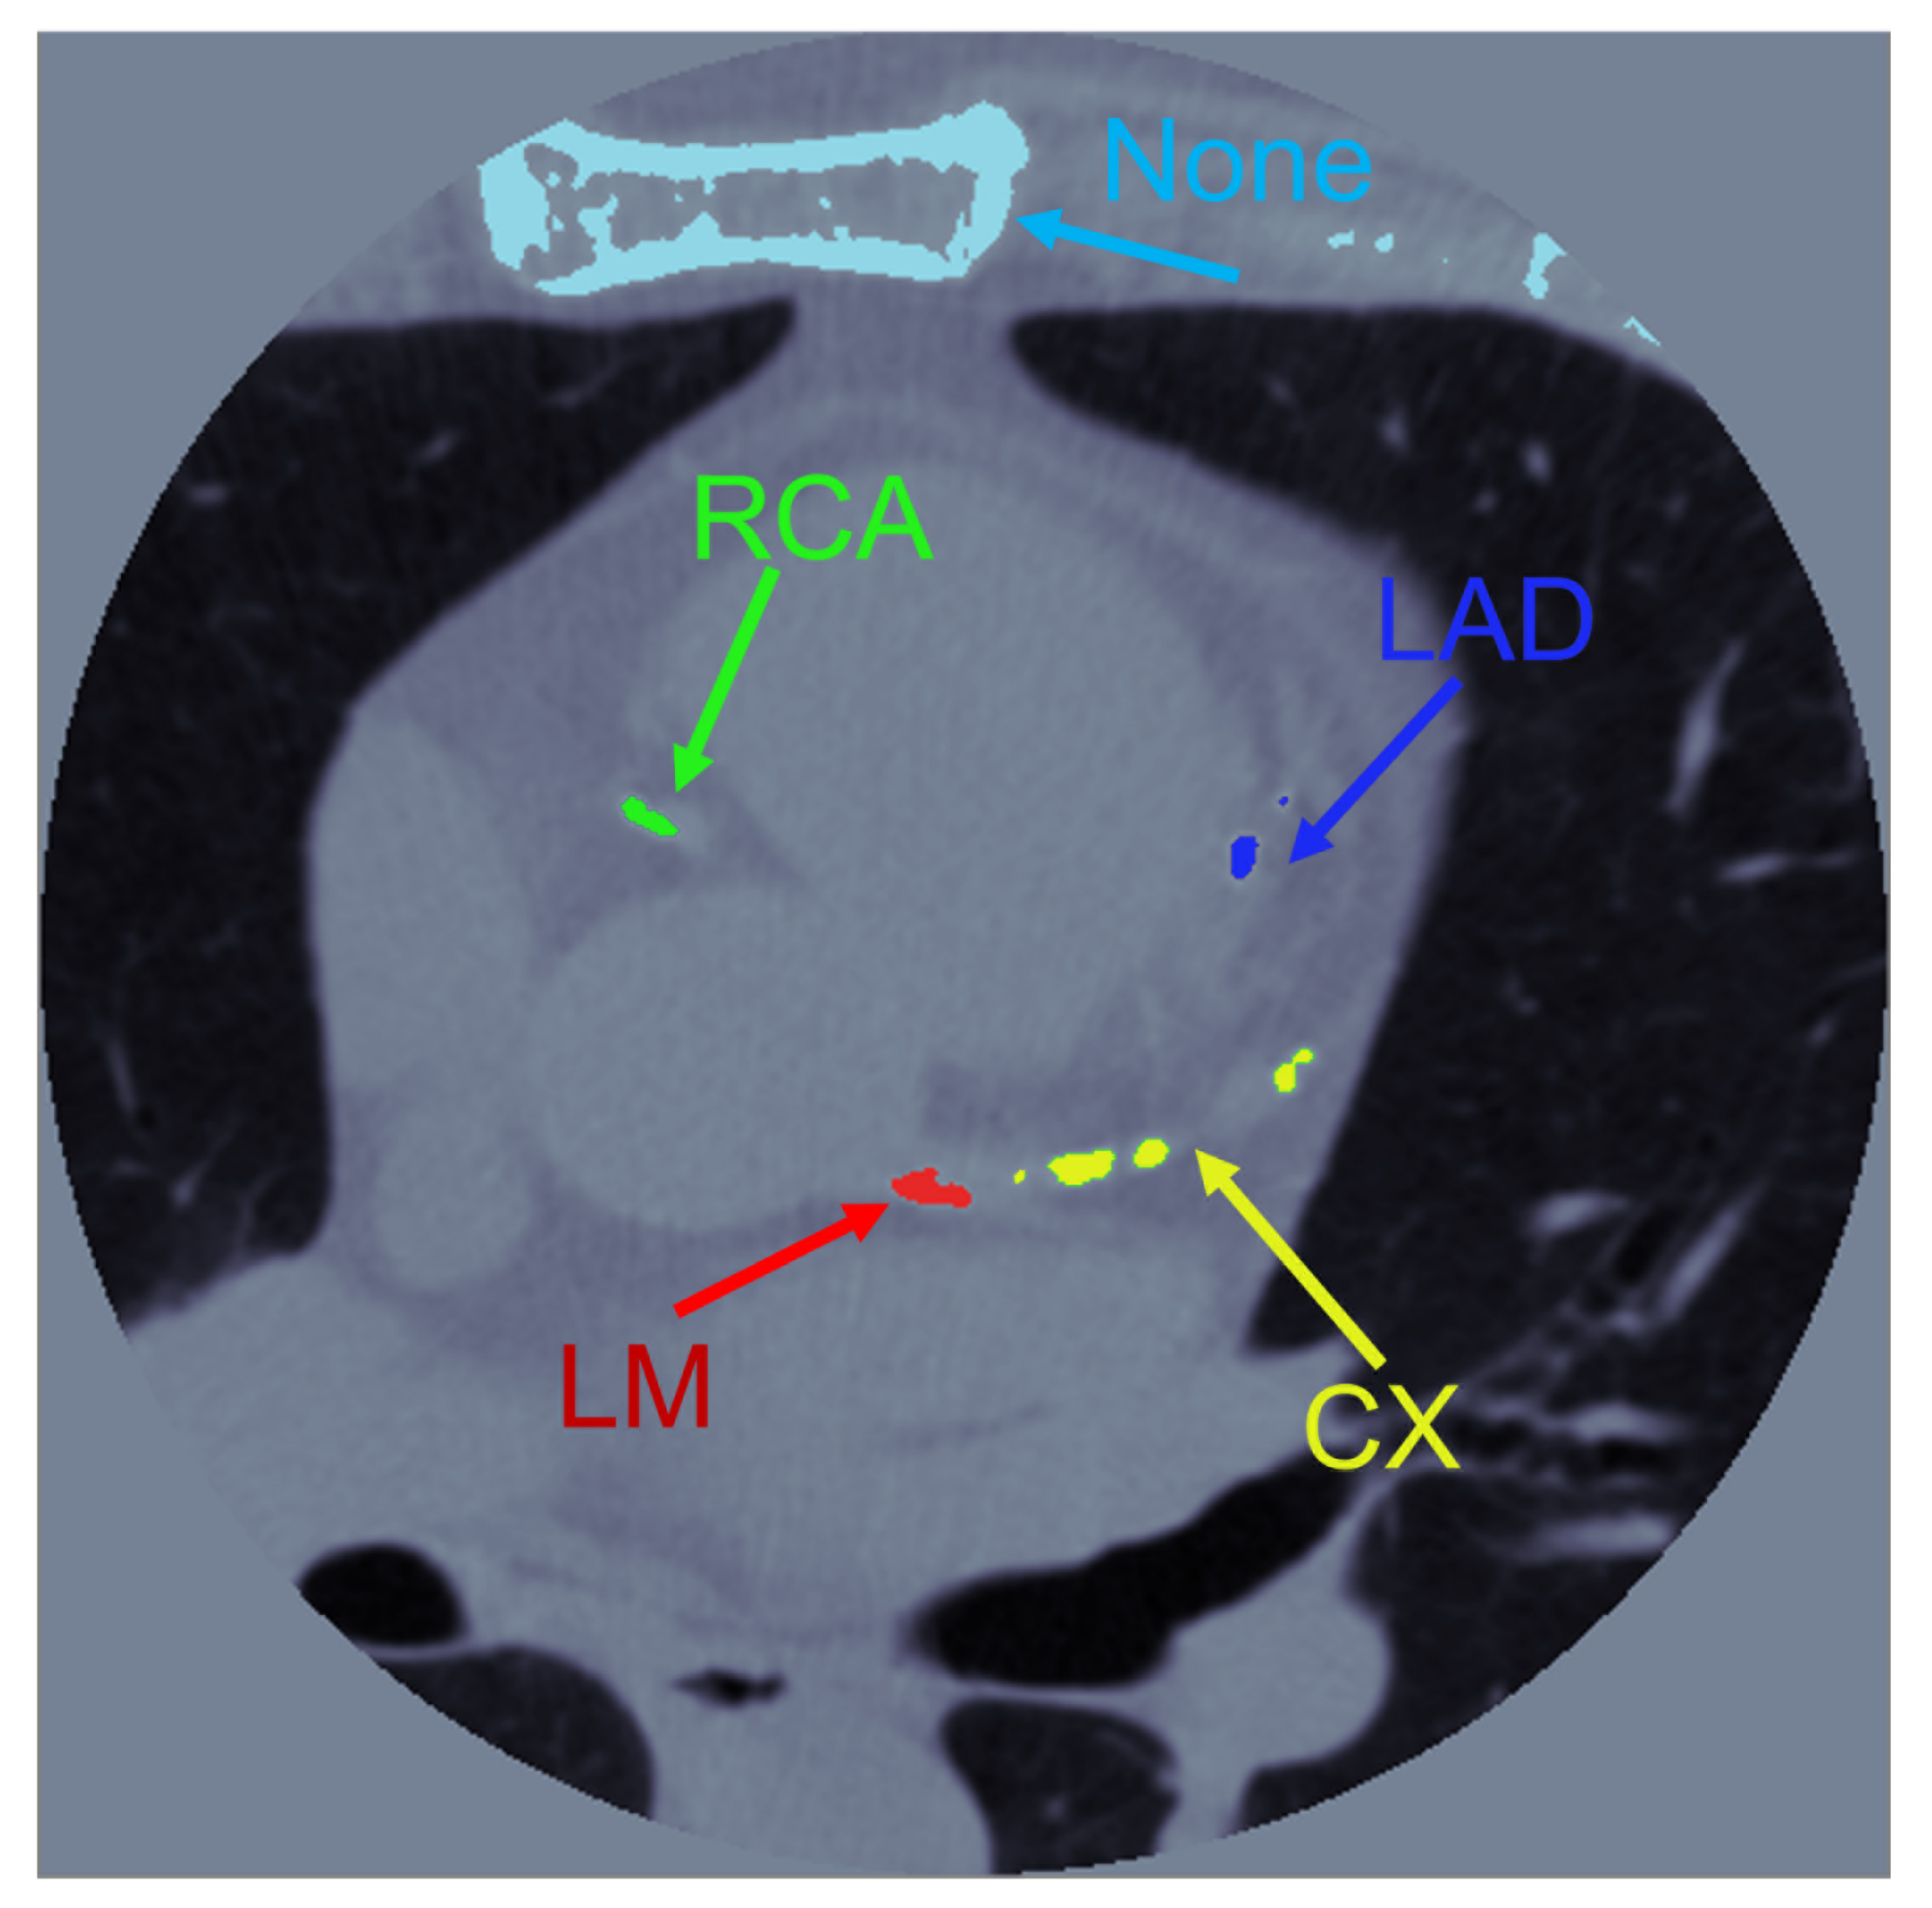

2.1. Calculation of the Coronary Calcium Score

2.3. Image Processing